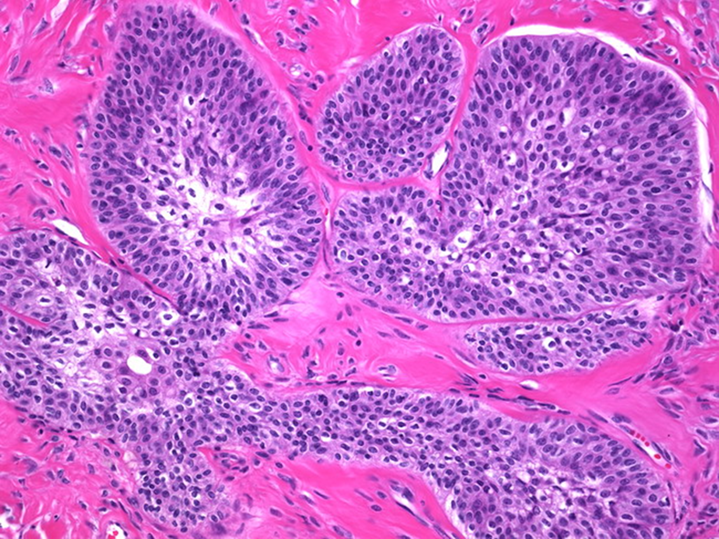

Brenner Tumor presents as urothelium nests within the ovary

→ are benign and are associated with mucinous cystadenoma